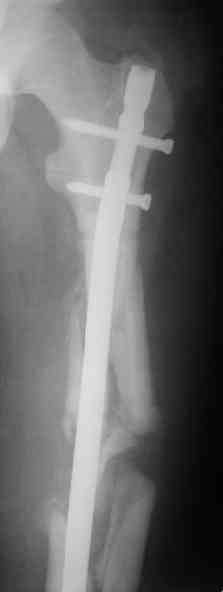

Судя по уровню перелома, винты в шейку избыточны, подойдет и диафизарный гвоздь. Все, что нужно, это тиски и труба. Загнуть сразу ниже отверстий градусов на 8-10, и вся недолга. Последние годы у нас это рутинная практика. Предызогнутые еще с завода гвозди неудобны тем, что они уже правый-левый.

Согласен, что закрытый реостеосинтез с рассверливанием и коррекцией оси - это то, что надо. Мы бы ввели в центральный отломок статических 2-3 винта, и один динамический винт в дистальном отломке.

Вот несколько. С тисками и трубой на днях сделаем.